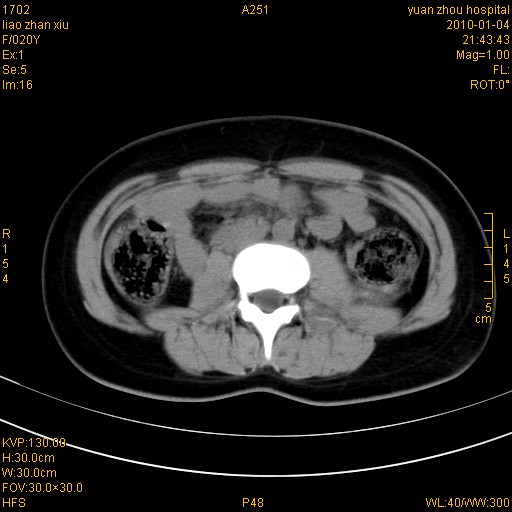

标题: CT23985:F20Y 外伤典型病例 [打印本页]

标题: CT23985:F20Y 外伤典型病例

左肾挫伤,包膜下积血,l3、4左侧横突多发骨折。

双侧肾胞膜下出血,左侧较多。l3、4左侧横突多发骨折。

2、l3、4左侧横突多发骨折;

左肾挫伤,包膜下积血,l3、4左侧横突多发骨折

气死我了,明明l1、2,为什么都说3、4.

左肾挫伤,包膜下积血,L1、2、3、4左侧横突多发骨折。